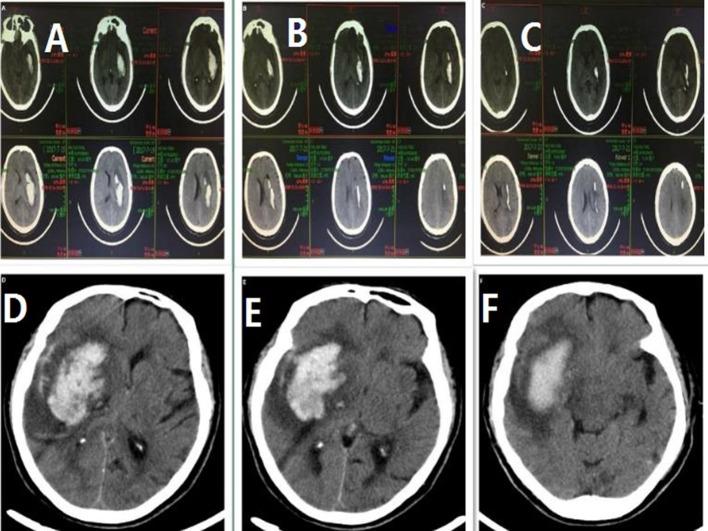

We aimed to compare the therapeutic effects of stereotactic aspiration and best medical management in patients who developed supratentorial hypertensive intracerebral haemorrhage (HICH) with a volume of haemorrhage between 20 and 40 mL.

The clinical data of 220 patients with supratentorial HICH with a volume between 20 and 40 mL were retrospectively analysed. Among them, 142 received stereotactic aspiration surgery (stereotactic aspiration group) and 78 received best medical management (conservative group). All were followed up for 6 months. Multivariate logistic regression and Kaplan-Meier survival curves were used to compare the outcome between the two groups.

The rebleeding rate was lower in the group that had stereotactic aspiration when compared with the group with medical treatment (6 [4.2%] vs 9 [11.5%], χ=4.364, p=0.037). After 6 months, although the mortality rate did not differ significantly between the two groups (8 cases [5.6%] vs 10 cases [12.8%], χ=3.461, p=0.063), the rate of a favourable outcome was higher in the group who received stereotactic aspiration (χ=15.870, p=0.000). Logistic regression identified that medical treatment (OR=1.64, p=0.000) was an independent risk factor for an unfavourable outcome. The Kaplan-Meier curves indicated that the median favourable outcome time in the stereotactic aspiration group was 59.5 days compared with that in the medically treated group (87.0 days). The log-rank test indicated that the prognosis at 6 months was better for those treated with stereotactic haematoma aspiration (χ=29.866, p=0.000). However, the 6-month survival rate was similar between the two groups (χ=3.253, p=0.068).

Stereotactic haematoma aspiration significantly improved the quality of life, although did not effectively reduce the rate of mortality. When selected appropriately, patients with HICH may benefit from this type of surgical intervention.